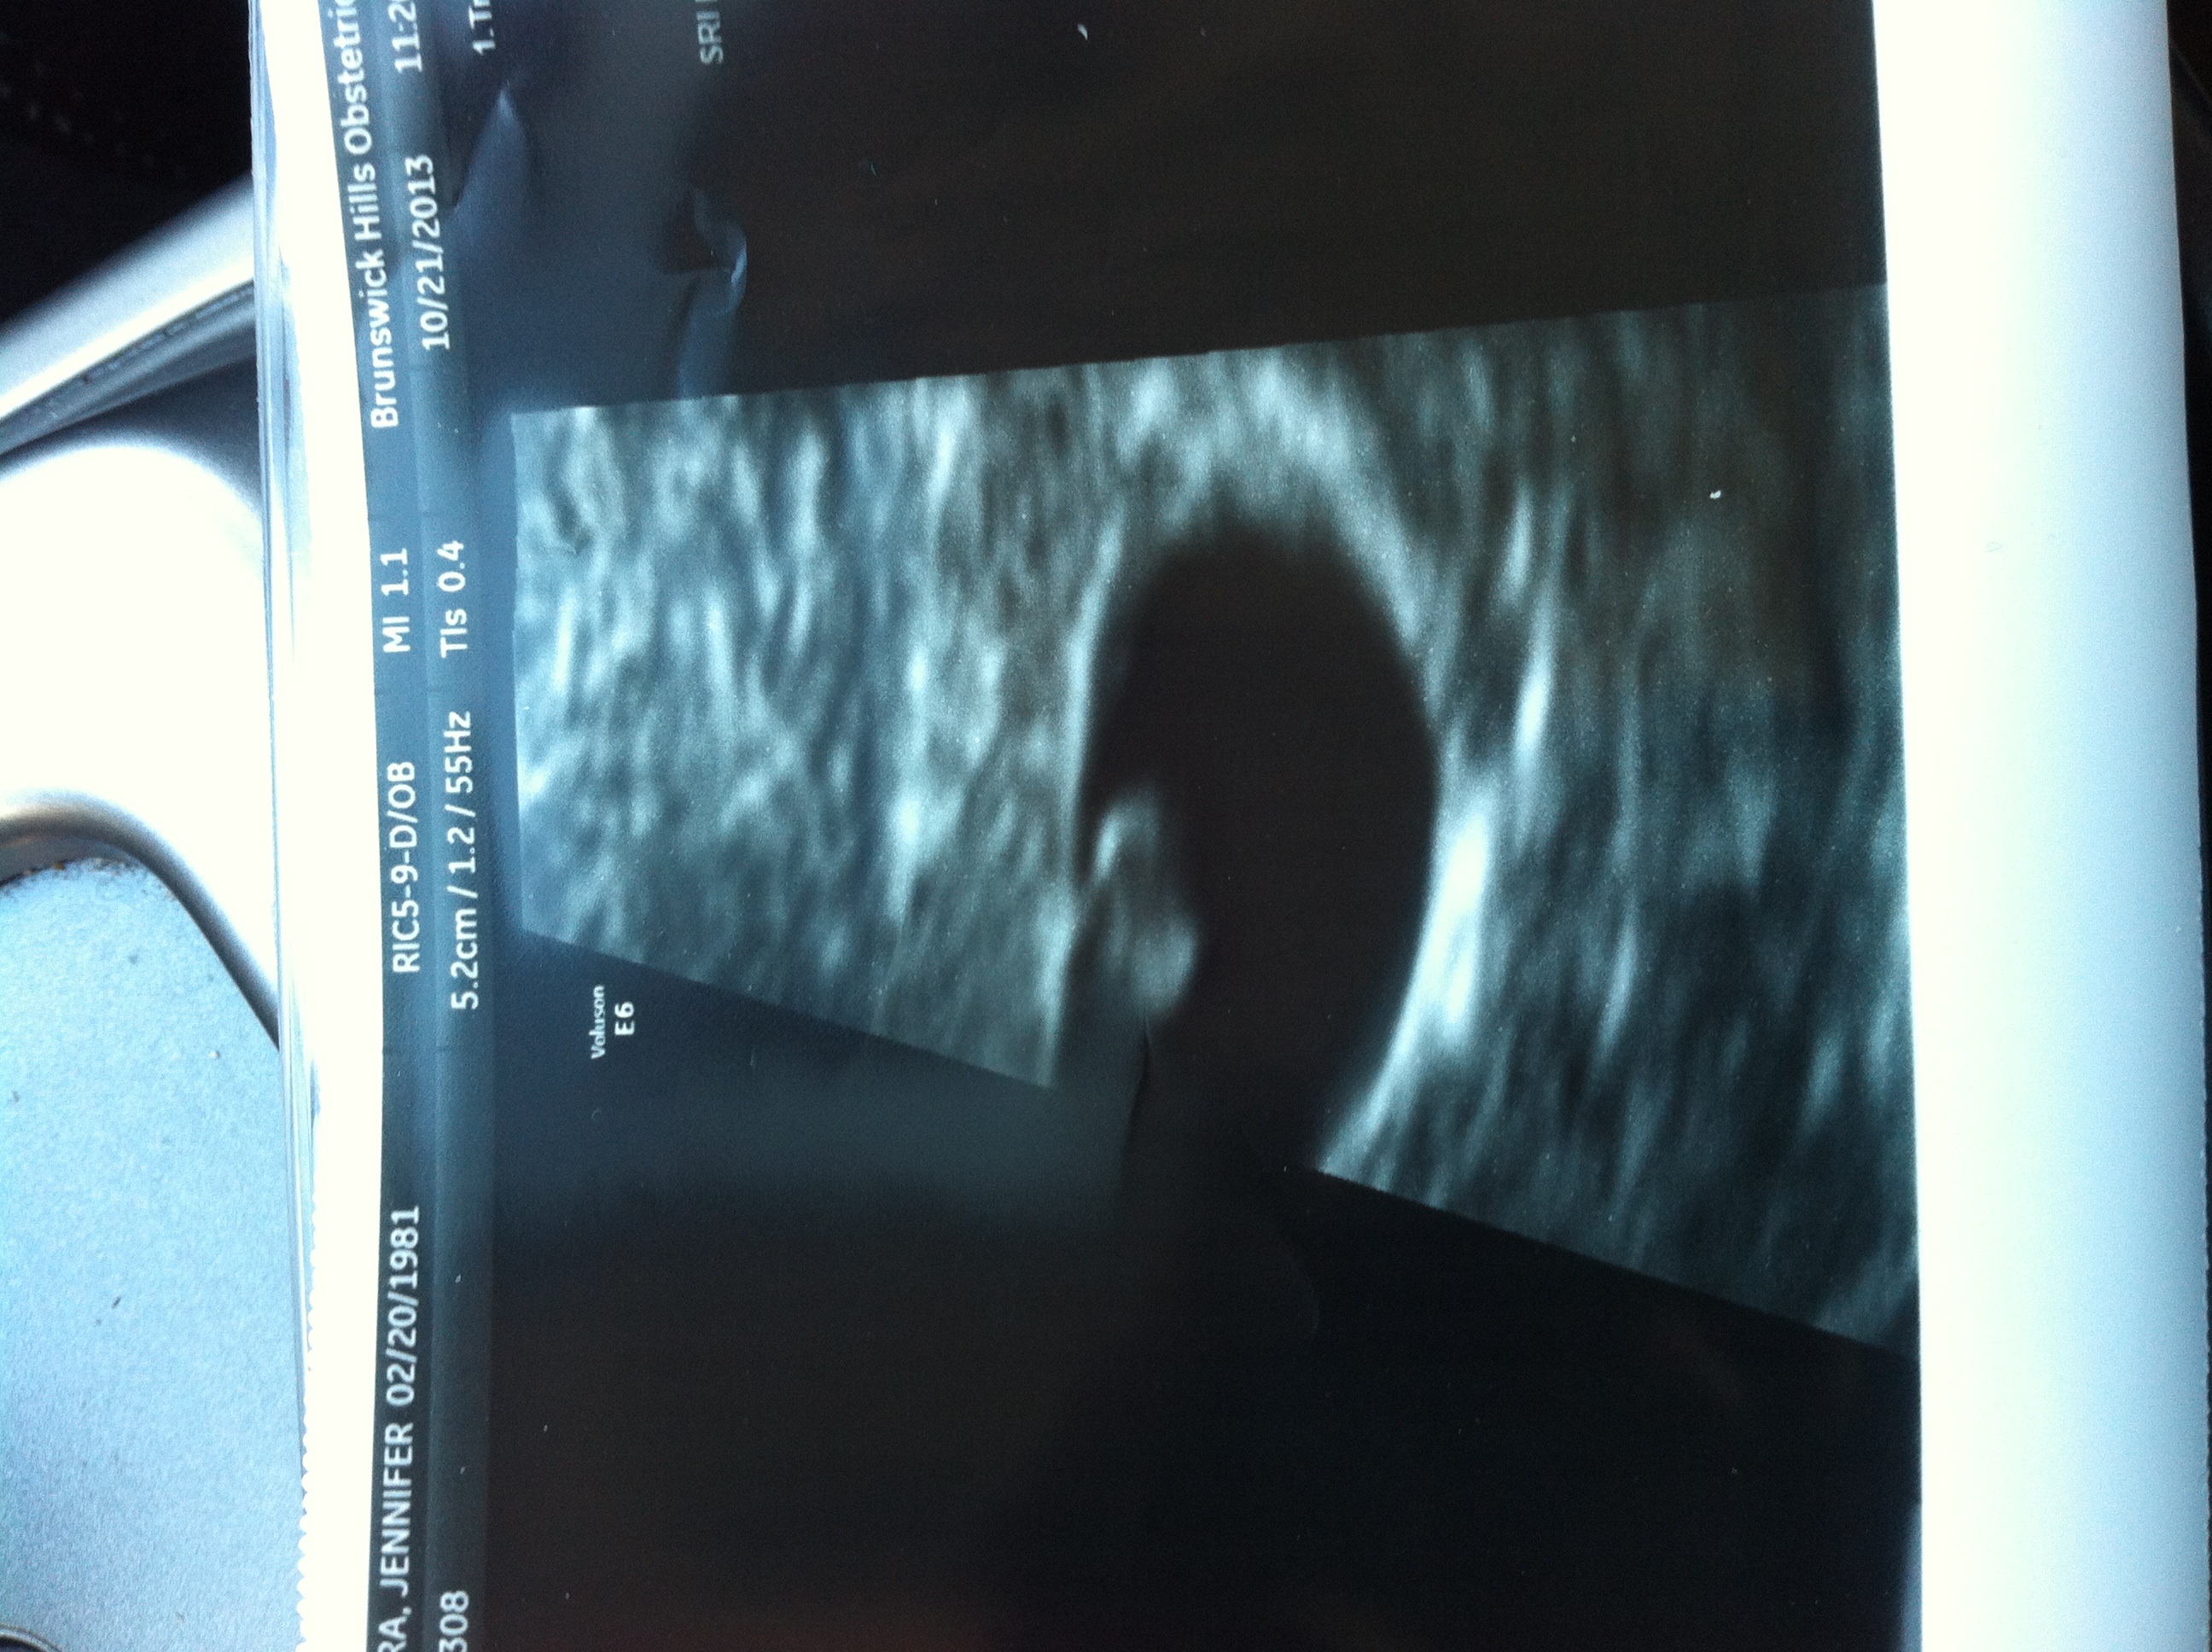

How are you feeling physically/emotionally? Updates/appointments?I'm feeling pretty positive today. Had an ultrasound this morning...our blob measured 6 weeks 6 days, with a heartbeat of 141. Such a relief to get good results! Doc (RE) said to keep taking the progesterone for a few more weeks, but he doesn't need to see me again unless I have any issues. We told my immediate family over the weekend and DH is going to tell his parents soon too, so it is starting to feel more real though I know it's still too early to be counting our chickens. Physically -- every day is different. Yesterday I felt like I had a raging hangover all day -- sour stomach, exhausted -- and today I felt pretty normal. Any PgAL crazy you want to add? Still talking in "ifs" and checking the TP. Good to know it's not just me. I'm not really into Halloween movies either, sorry to say. But I do love to see trick or treaters and hope to get a bunch in our new neighborhood!

Any updates or appointments coming up you'd like to share? Ultrasound and appt 10/17 went great - there was a baby bean measuring about 6w6d with a good heart rate according to my doc! EDD is officially 6/3 based on LMP, I'm not measuring far enough off to go by O date instead. Get to go back Friday 10/25 for a follow up ultrasound and appt...hopefully all is looking well!

10/17: U/S shows healthy bean @ 6w6d, HR 119 10/25: U/S shows bean is growing @ 8w0d, HR 158!